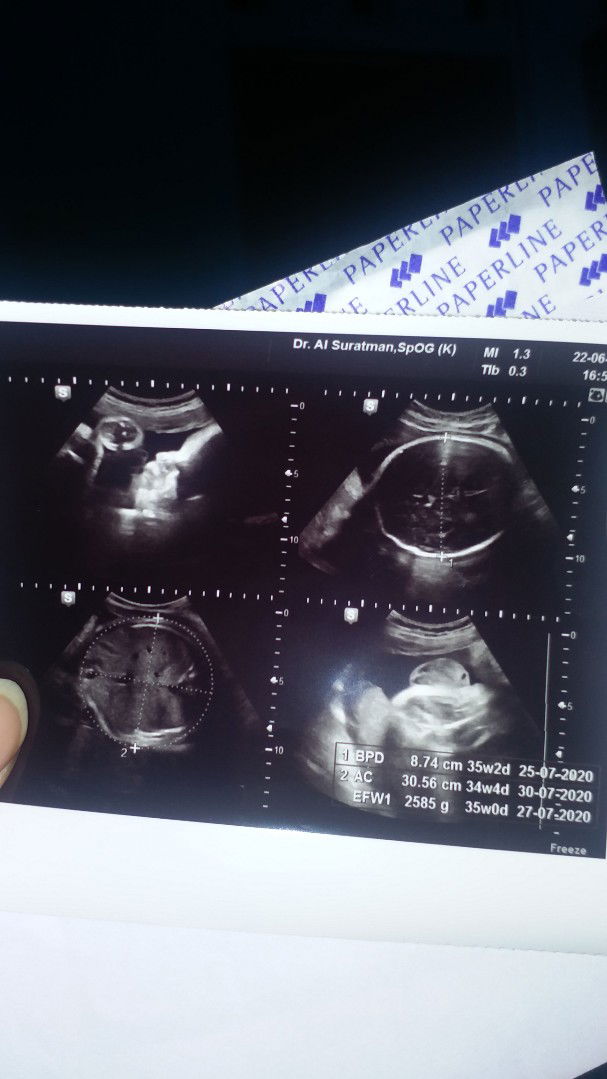

HPL 20 juli, UK dah 36 weeks, tapi pas di usg panjang janin 30.56 cm. Normal gk sih bund